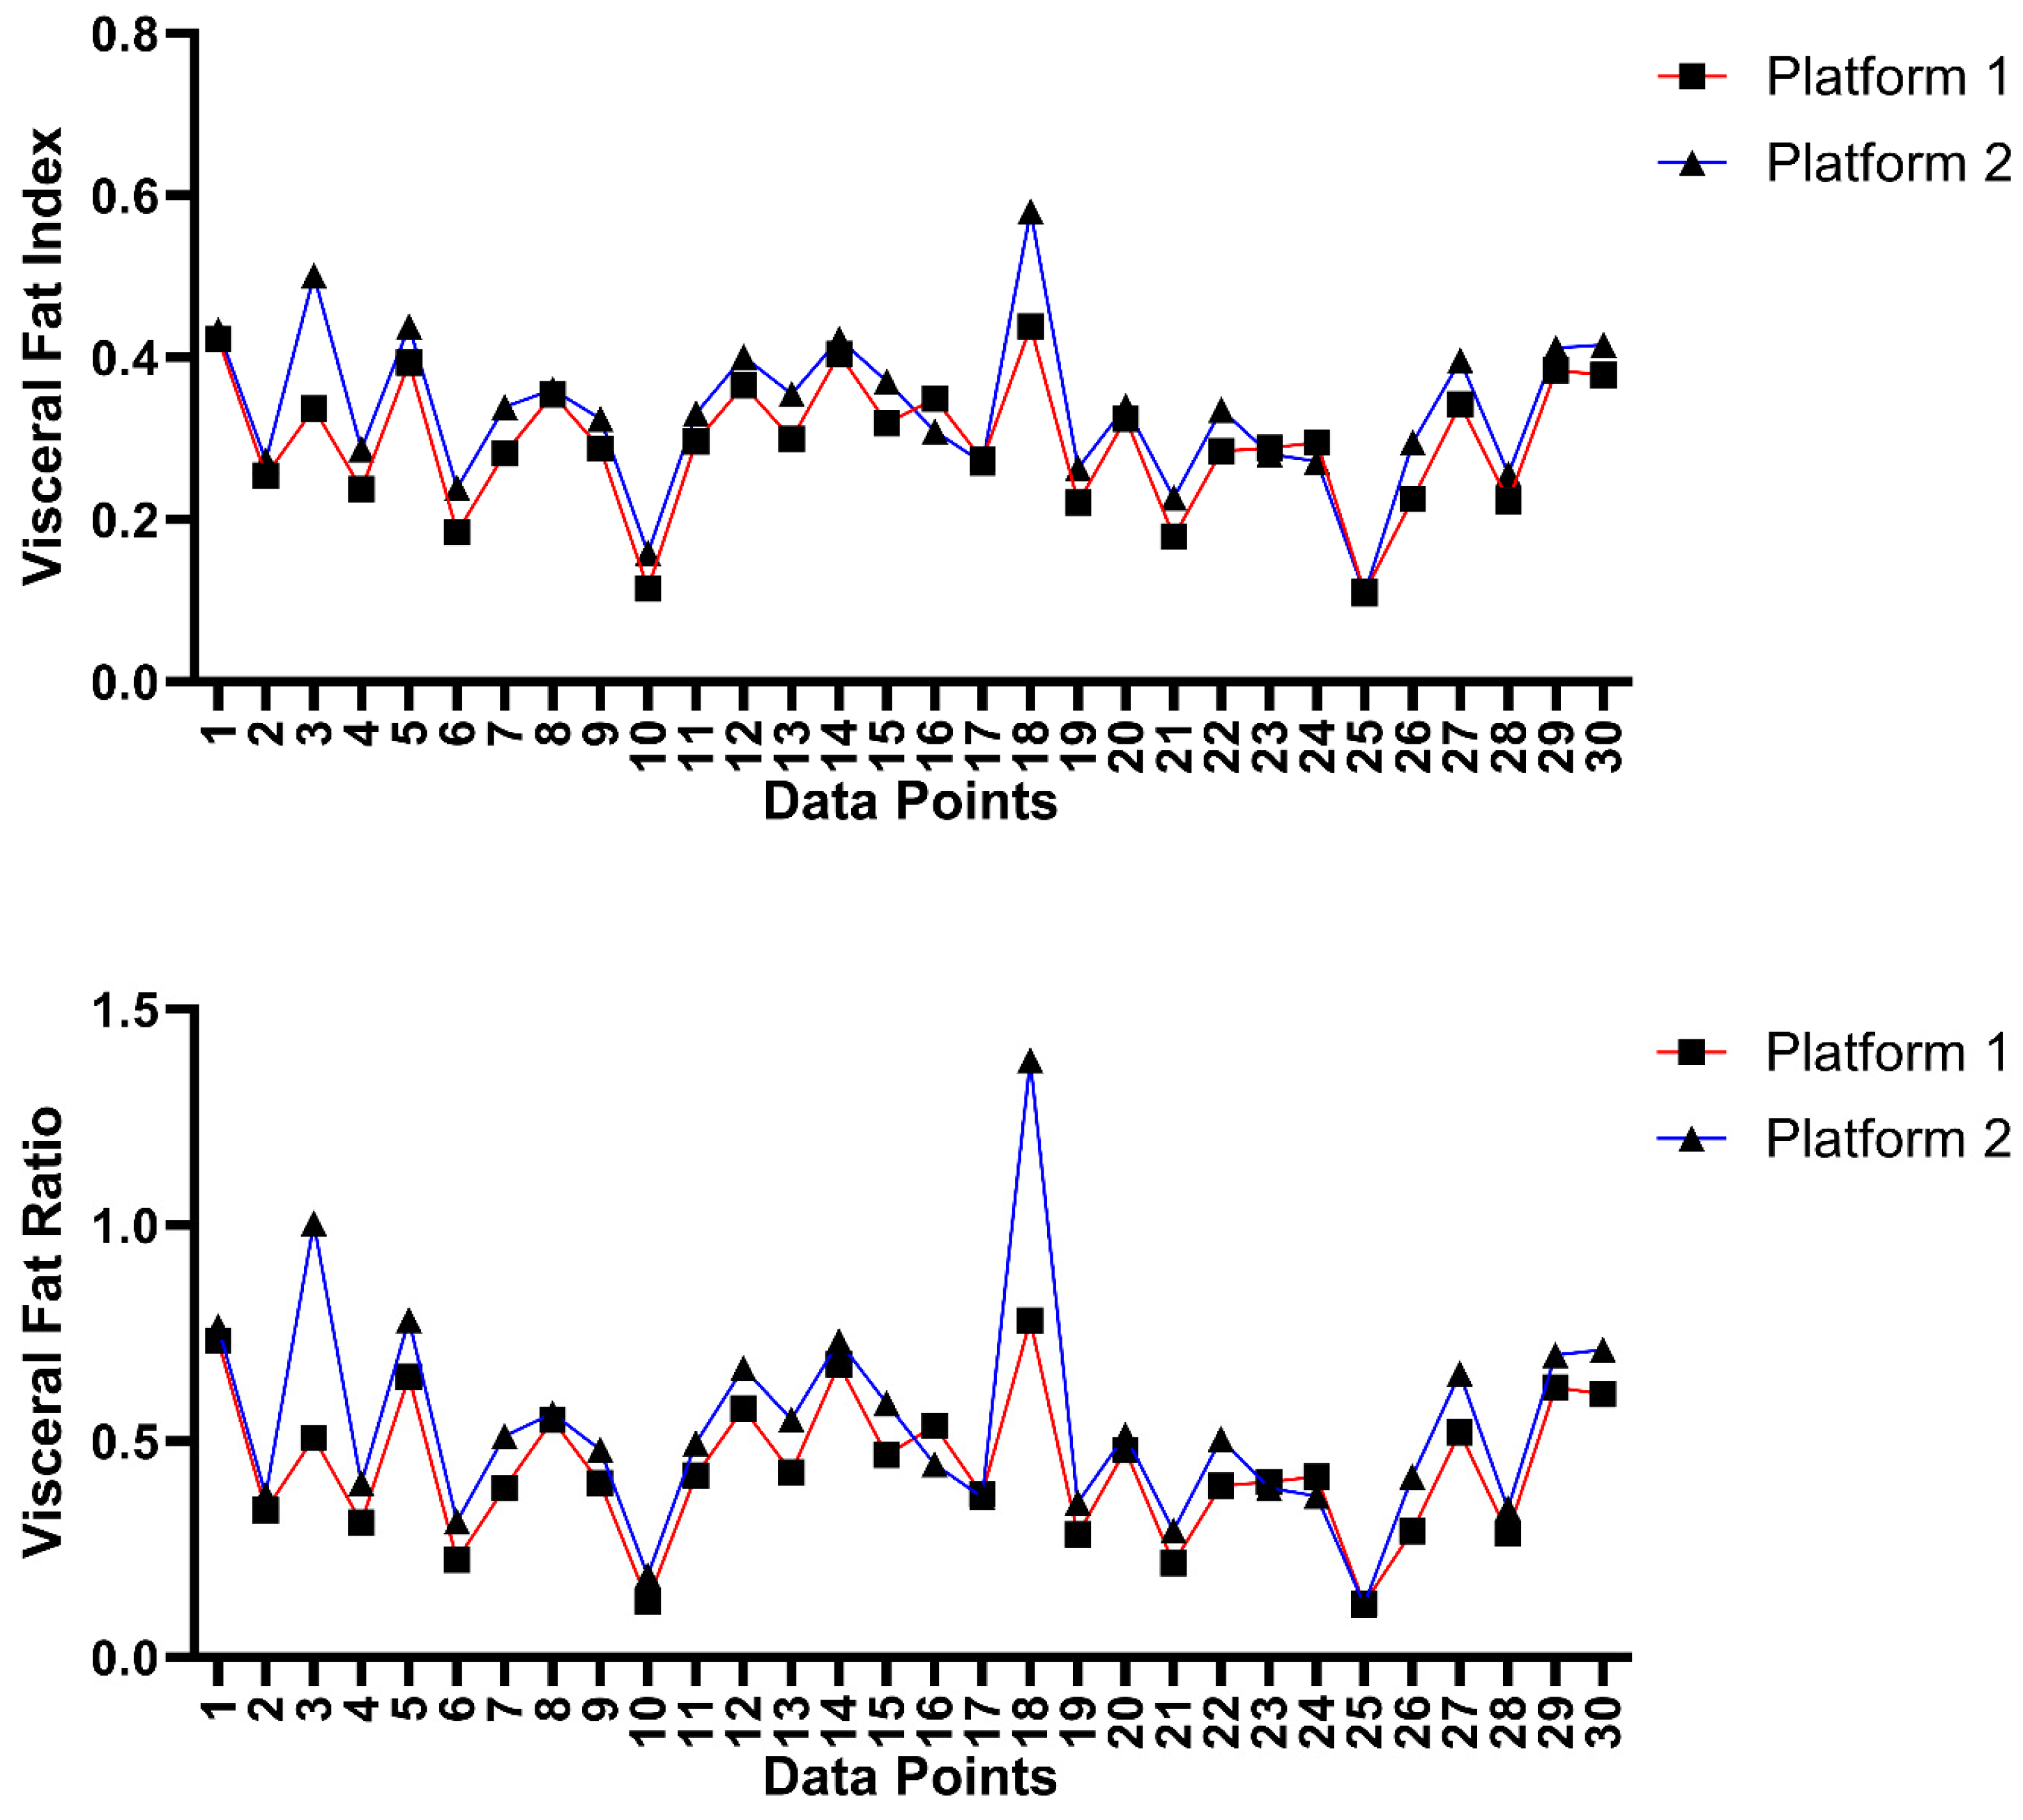

3.4. Inter-Platform and Inter-Rater Analysis